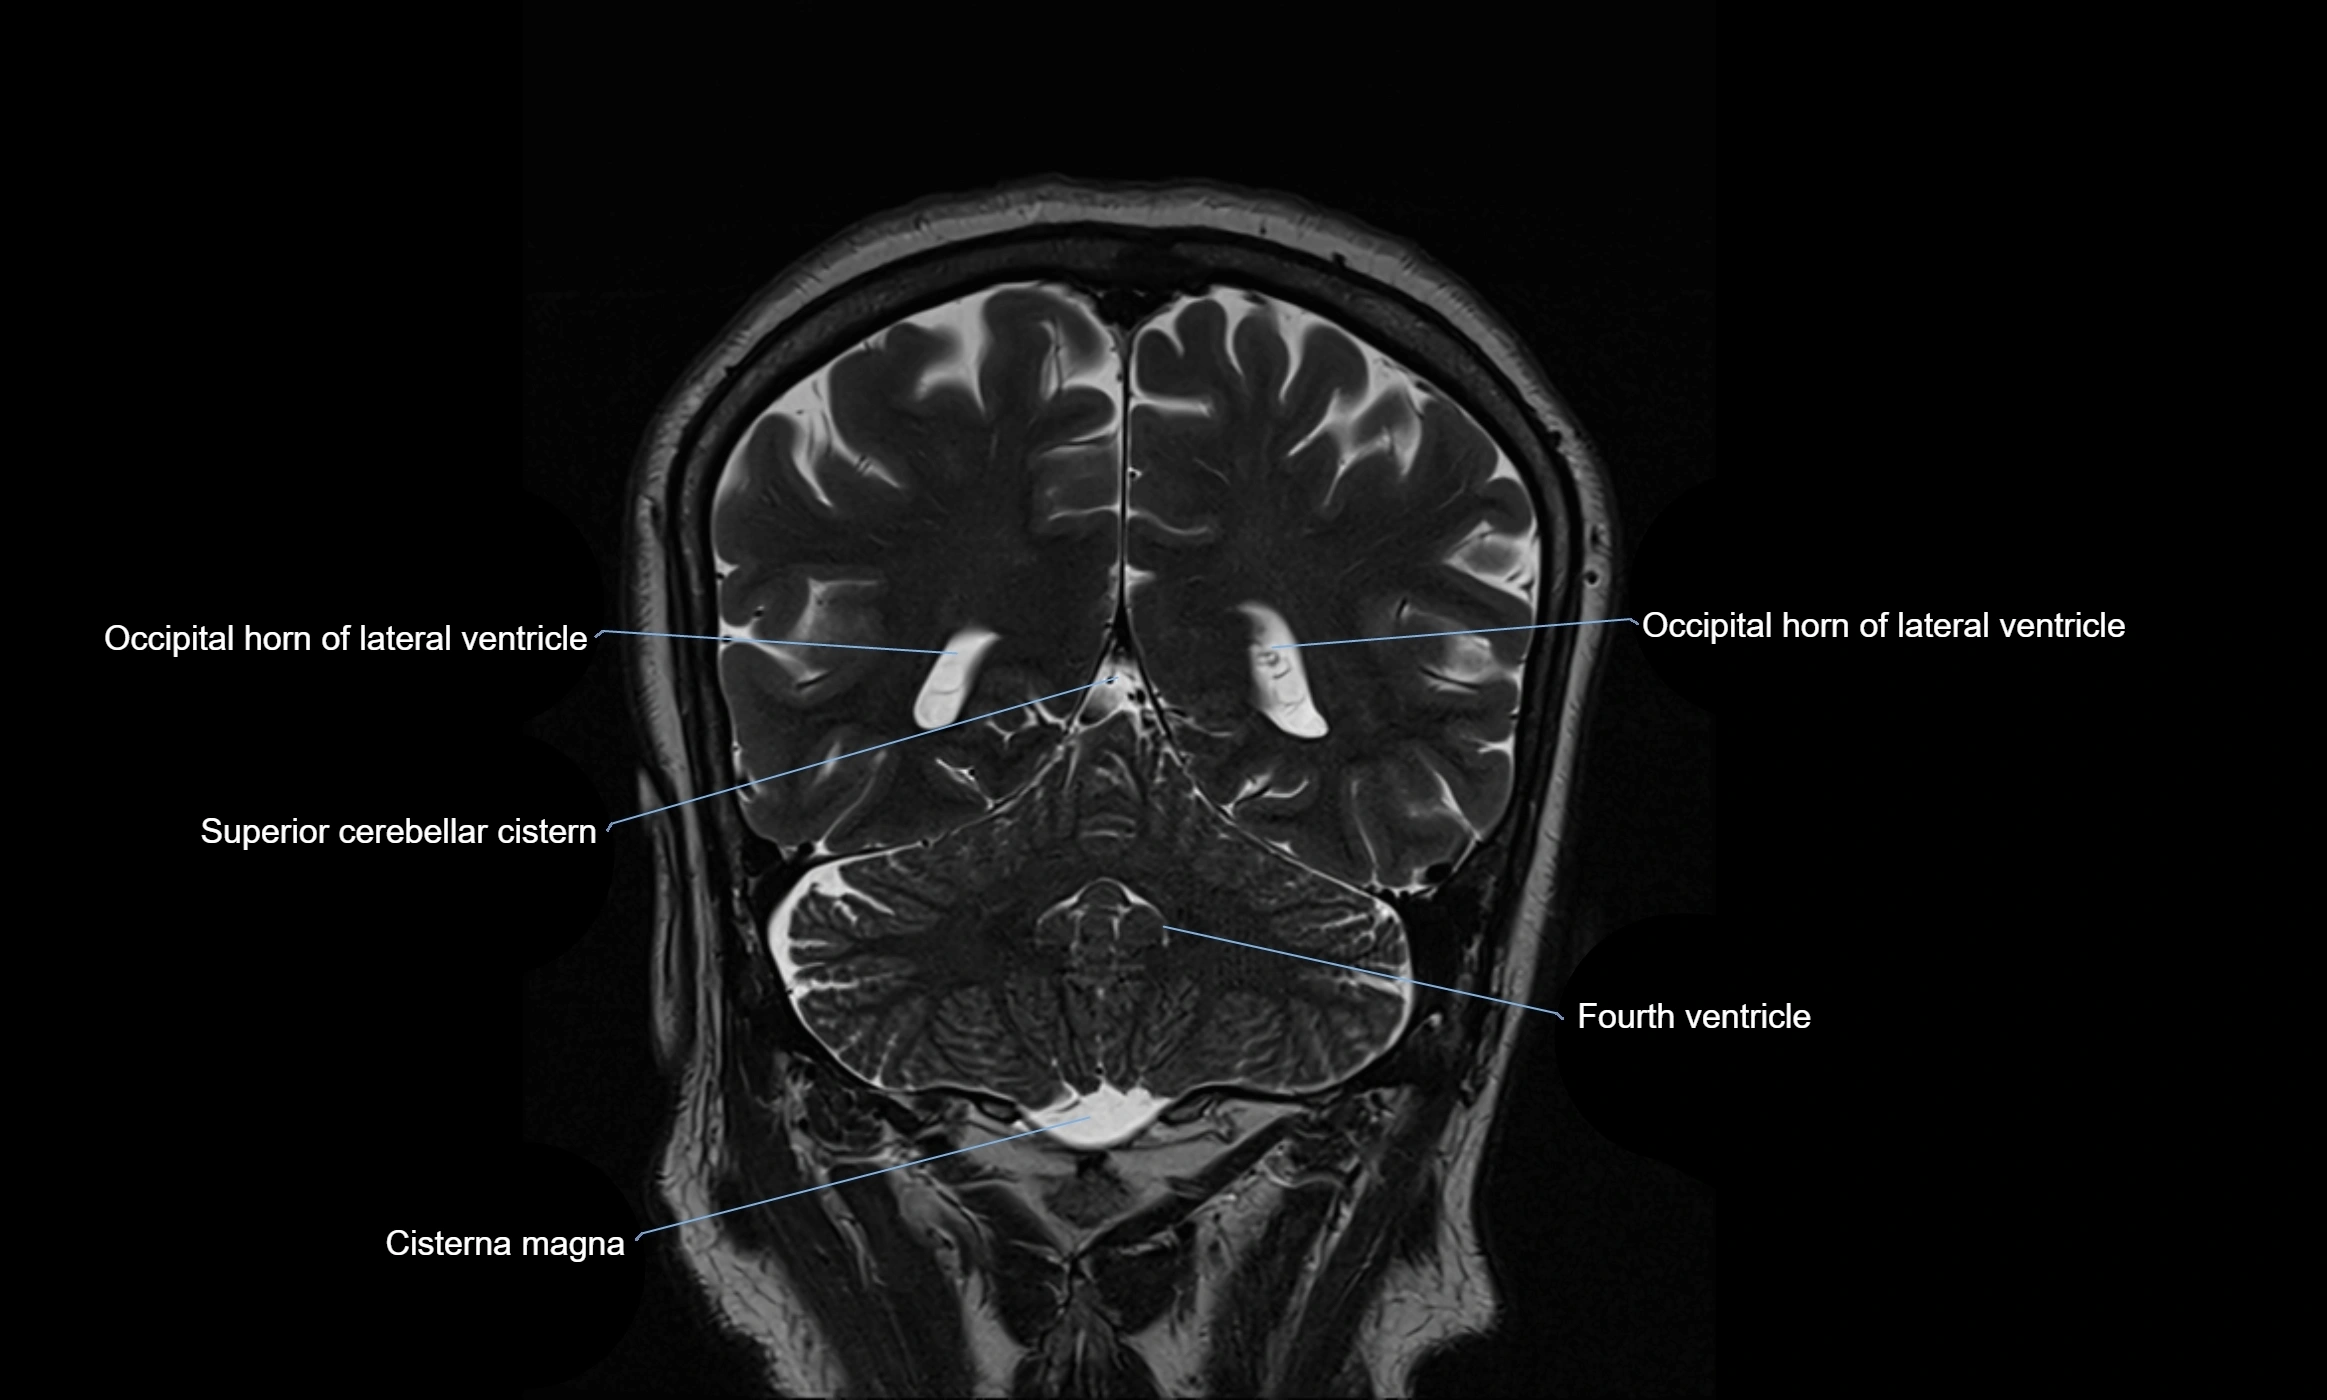

MRI images

image